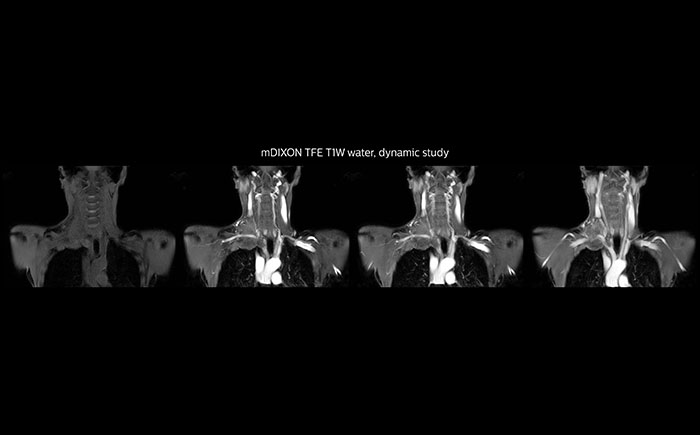

MRI of Pancoast tumor

Although the area between the neck and the top of the lung is one of the most difficult areas for MRI, Prodiva 1.5T images show good quality in this 56-year-old male with Pancoast tumor on the right. mDIXON TFE images shows excellent fat suppression in the neck area and the DWI shows almost no distortion.

MRI of Pancoast tumor

Although the area between the neck and the top of the lung is one of the most difficult areas for MRI, Prodiva 1.5T images show good quality in this 56-year-old male with Pancoast tumor on the right. mDIXON TFE images shows excellent fat suppression in the neck area and the DWI shows almost no distortion.